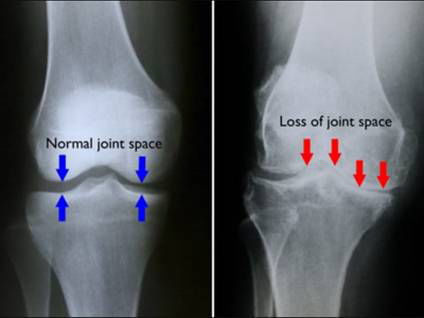

- Stadiul III: deja vorbim de o gonartroza destul de grava, cartilajul articular prezinta leziuni, iar spatiul articular apare pe radiografie ingustat; apar durerile, se umfla articulatiile, mai ales dupa mers prelungit. Daca in primele doua stadii tratamentul se baza pe cel kinetoterapeutic, de data aceasta fizioterapia are rezultate mediocre; se administreaza medicatie nesteroida, analgezice, infiltratii intraarticulare cu substanta vascoelastica, cu acid hialuronic sau PRP, efectul fiind resimtit dupa aceste infiltratii la cateva zile.

- Stadiul IV : este o gonartroza severa cu dureri mari, in care spatiul articular este mult redus, distrugerea cartilajului articular, cantitatea de lichid articular este extrem de diminunat, apare deja frictiunea dintre cele doua extremitati osoase care duce la invaliditatea bolnavului.